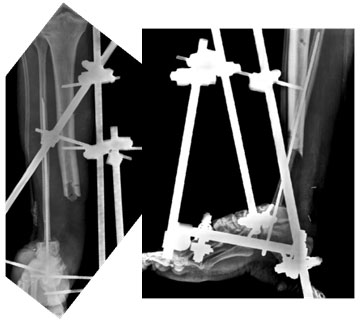

4 months

4 months post surgery. The xrays show progress of healing at the talo-fibular junction. There is formation of bony connection between cut end of tibia and fibula, helping in the transmission of weight from tibia to the fibula. |

| 6 months |

| 6 months post surgery – x-rays show good healing at the talo-fibular junction and consolidation of extra bone at tibio-fibular junction. |